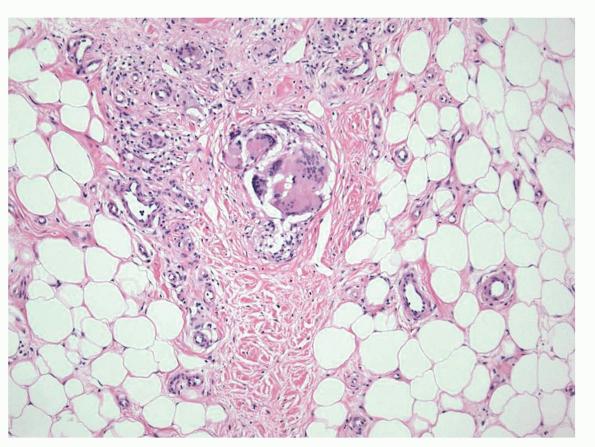

In the early lesions of acute erythema nodosum, there is edema of the septa with a Iymphohistiocytic infiltrate, having a slight admixture of neutrophils and eosinophils . Focal fibrin deposition and extravasation of erythrocytes occur frequently  and can be revealed by spectral microscopy . Often, the inflammation is most intense at the periphery of the edematous septa and extends

into the periphery of the fat lobules between the individual fat cells in a lacelike fashion. Necrosis of the fat is not prominent. Rarely, clusters of neutrophils are present or the infiltrate is predominantly neutrophilic . Clusters of macrophages around small blood vessels, or a slitlike space, occur in early lesions and are known as Miescher's radial nodules . Some authors have failed to find central vessels  and have considered Miescher's nodules to be characteristic of erythema nodosum, stating that they can be found in all stages of erythema nodosum . The degree of vascular involvement is variable . Usually, there is edema of the walls of veins with separation of the muscular layers . Infiltration by lymphocytes is common, but neutrophils and eosinophils can be present as well. Necrosis of the vessel walls is very rare but has been observed in a few patients with lesions clinically indistinguishable from erythema nodosum . For example, focal vasculitis has been found in a few patients with acute erythema nodosum secondary to infections  and in a few cases of recurrent

erythema nodosum that is secondary to medications or estrogenic oral contraceptives.

Later lesions of acute erythema nodosum show widening of the septa, often with fibrosis and with inflammation at the edges of the septa and involving the periphery of the fat lobules . Neutrophils usually are absent, and the vascular changes are less prominent than in early lesions. There are more macrophages in the infiltrate. Macrophages at the edges of the fat lobules show phagocytosis of lipid from damaged adipocytes, and the small droplets of lipid in their cytoplasm give them a "foam cell" appearance. Granulomas formed by macrophages, without lipid deposition, are more frequent

when late lesions are compared with early ones . The granulomas often are loosely formed with macrophages predominating in a focus with multinucleated giant cells. Occasionally, well-formed, discrete sarcoidal granulomas occur in small numbers in the septa. The multinucleated cells usually have an irregular distribution of the nuclei in the cytoplasm. The oldest lesions have septal widening and fibrosis with a decrease in all of the inflammatory cells.